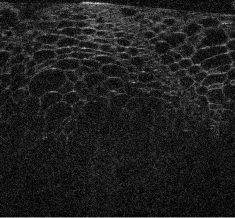

Visualizations of cross sectional reconstructions from the sub-sampled measurements are shown in Figure 2 and Figure 3 for the beaded gel and cucumber tissue samples respectively. Quantitative results of the NCC are then shown in Table 1.

| interpolated ISAM | MBIR TV | MBIR DT-CWT | |

|---|---|---|---|

|

random |

![]() |

equispaced |

partial |

From Figure 2, it appears that enhancement of the image structure is improved in each instance of MBIR. Random sub-sampling results in the best preservation of structure, followed by equispaced, and finally partial, which exhibits strong artifacts in each case. TV regularization appears to reasonably robust, but exhibits some block-like image artifacts, whilst DT-CWT has better preservation of speckle structure.